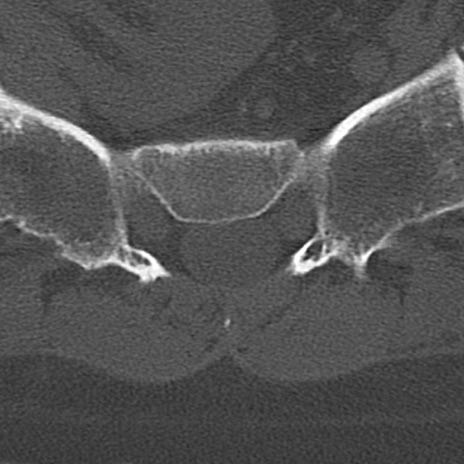

腰椎CT

横断像と矢状断像